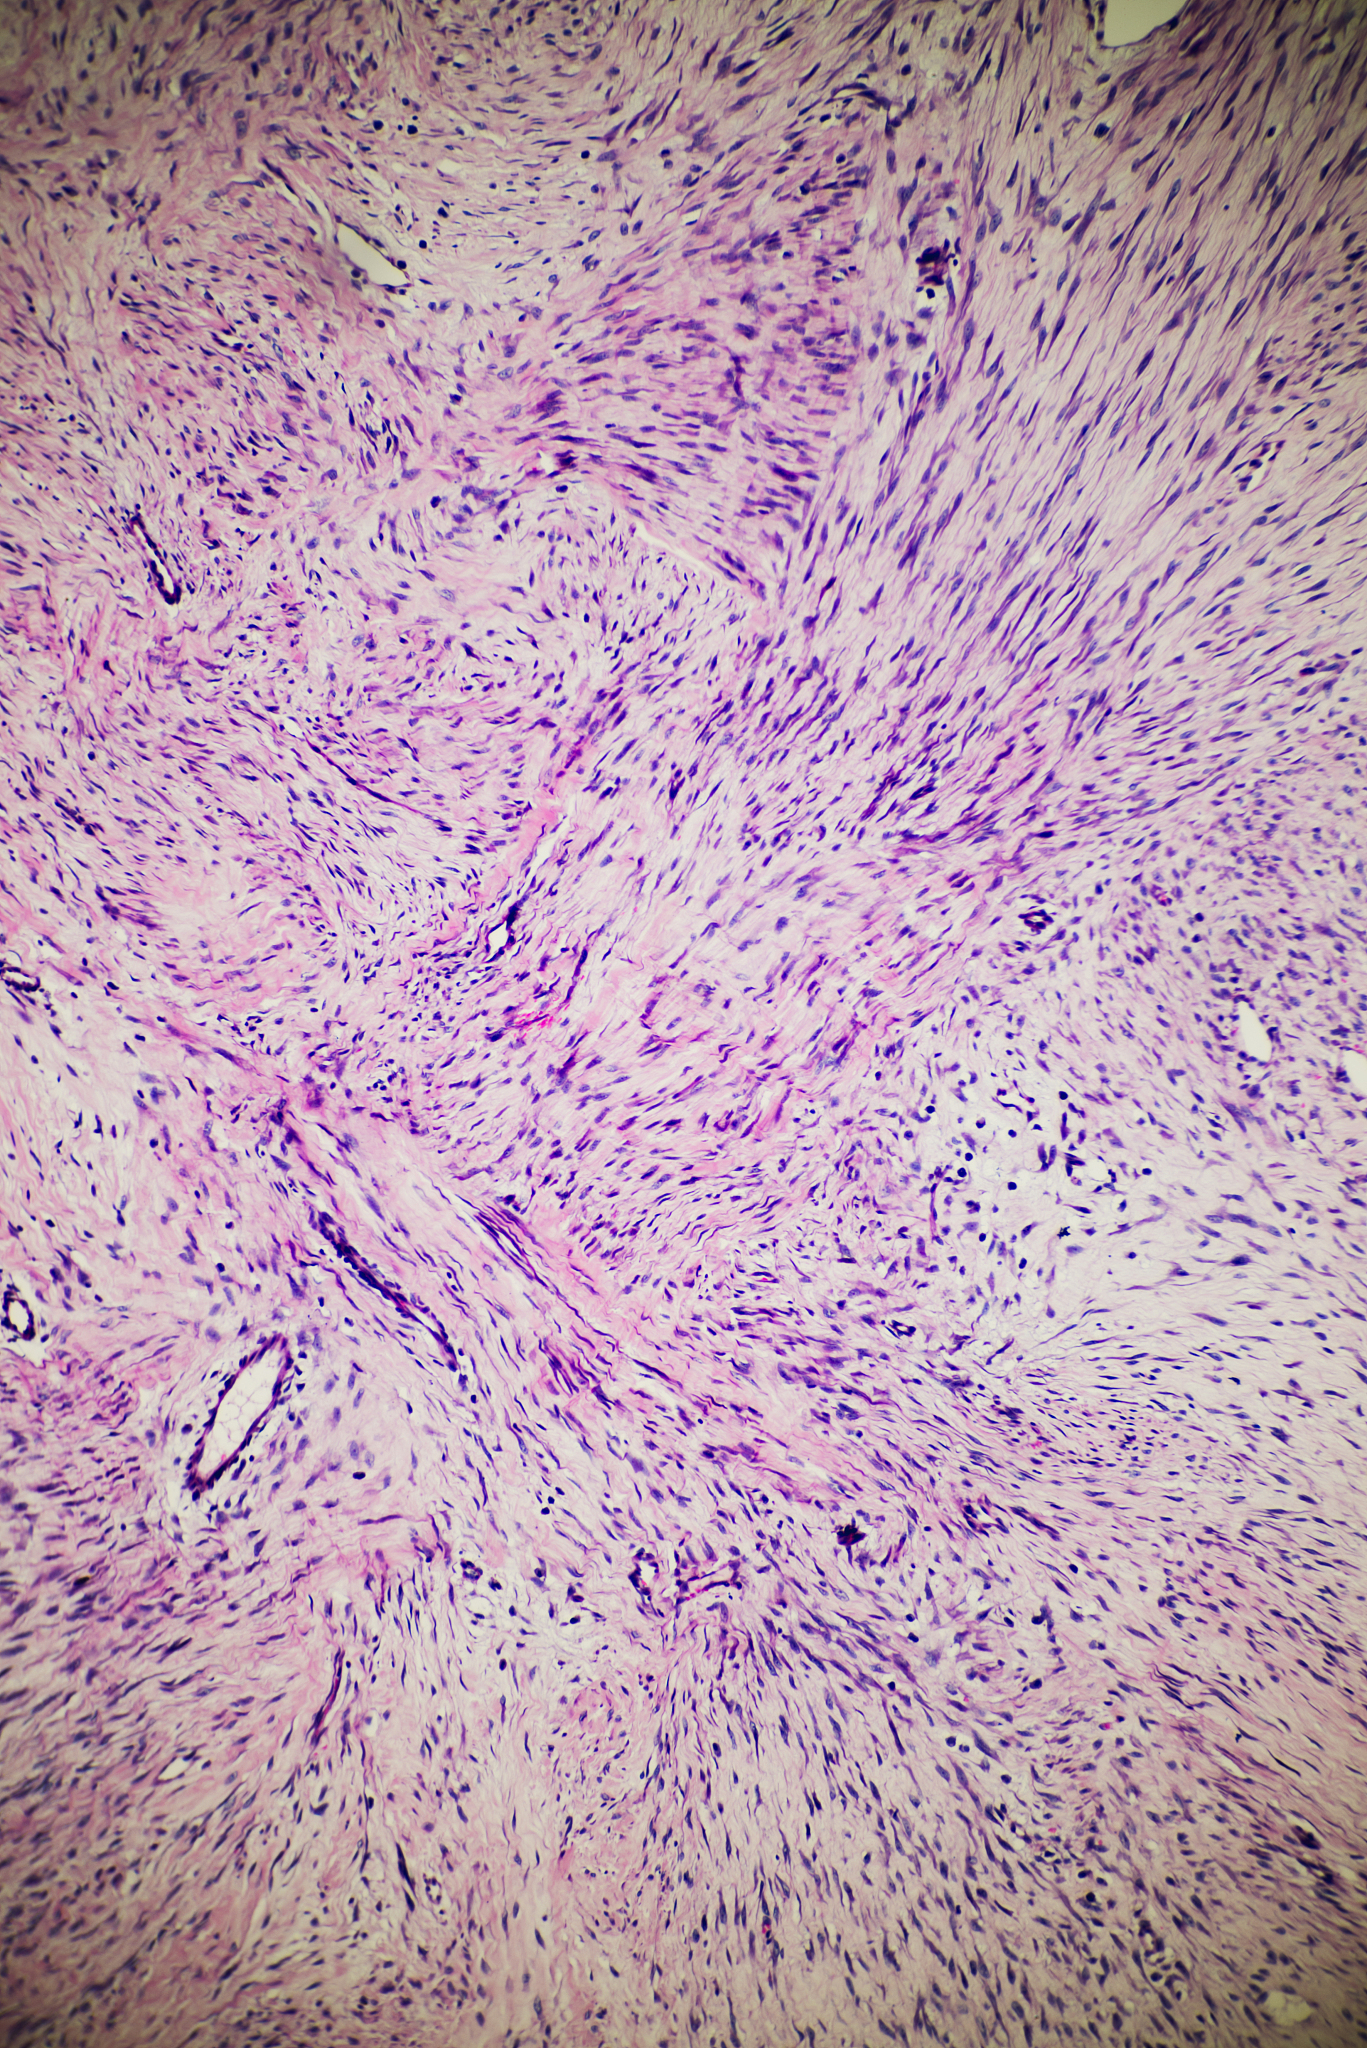

病理学特征

对子宫肌瘤和恶性肿瘤的明确诊断需要组织病理学检查。子宫肌瘤由平滑肌细胞和成纤维细胞组成,呈旋涡状排列。它们通常界限清楚,有包膜,没有侵入周围组织。另一方面,恶性肿瘤的特征是存在异常细胞,这些细胞表现出恶性特征,例如核异型、有丝分裂增多和侵入周围组织。